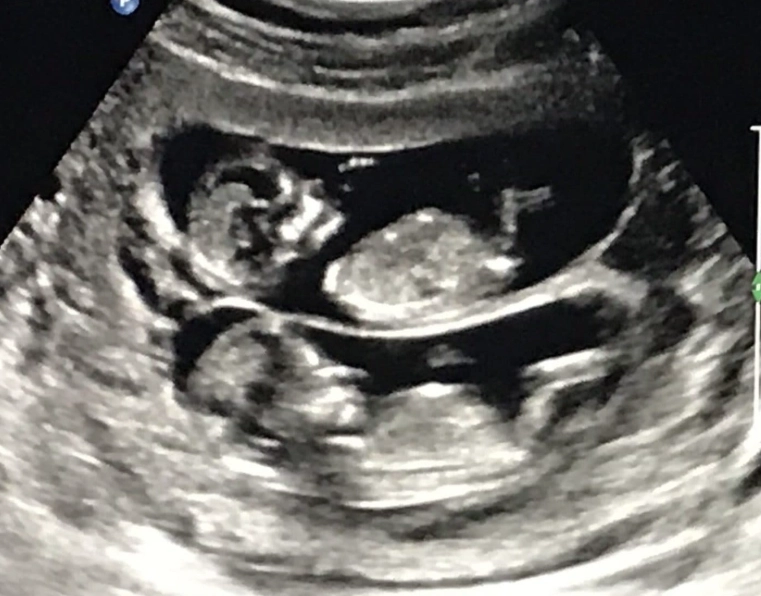

This is often the first detailed look at your baby, and it's breathtaking. The 12-week scan, sometimes combined with the First Trimester Screening (which assesses risk for chromosomal conditions), gives you a clear picture of that little occupant.

On the screen, you'll see your baby's location clearly within the amniotic sac inside the uterus. The sonographer will measure the baby from crown to rump to confirm your due date. They'll check for the presence of a nasal bone and measure the nuchal translucency—a small fluid space at the back of the baby's neck. An increased measurement can be a soft marker for certain conditions.

Beyond the medical checks, you'll get to see your baby in action. You might see the heart beating rapidly (around 120-160 beats per minute), watch the baby bring its hand to its mouth, or see it bounce gently against the uterine wall. It makes the whole thing feel wonderfully real.